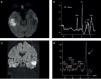

Finalmente un punto muy interesante es la utilización de la DWI en el seguimiento de pacientes con AC tratados con antibióticos sin drenaje quirúrgico. Esta herramienta resulta una de las más importantes para evaluar el éxito del tratamiento elegido, ya que presenta un descenso de la señal central, si la terapia antiobiótica tiene el efecto esperado; y la desaparición total, si el drenaje quirúrgico es completo27 (fig. 6).

Absceso cerebral bacteriano tratado con antibióticos: seguimiento. Paciente tratado con triple plan de antibióticos (ATB) debido a la ausencia de focalidad neurológica y el tamaño del absceso. En el estudio diagnóstico se observa el aspecto típico de la lesión: (a) edema en FLAIR, (b) realce anular en la secuencia ponderada en T1 con contraste e (c) intensa restricción en la difusión. En la RM de control a los 15 días se observa (d) la disminución del tamaño de la lesión y del edema, (e) la persistencia de un sector de realce y (f) sobre todo la ausencia total de restricción, que confirma la excelente respuesta al tratamiento instaurado.